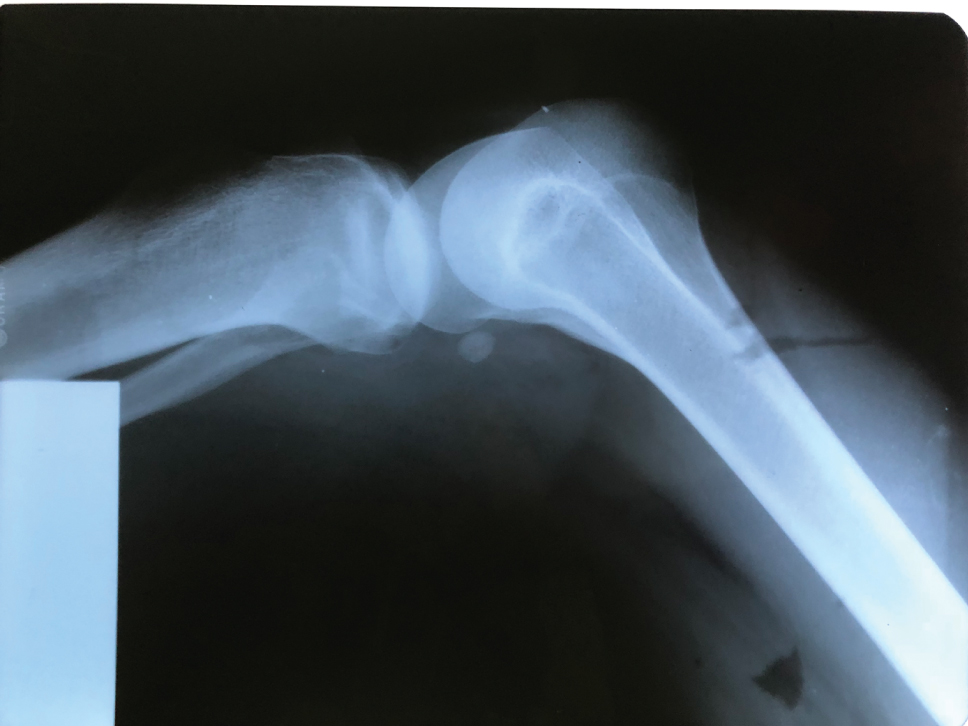

The patient was diagnosed as having nail-patella syndrome at the age of 12 years after admission to the hospital for symptoms related to rib deformities and nail hypoplasia. The syndrome-related symptoms included nail hypoplasia in the upper extremities, decreased flexibility at the elbow joints, contractures at both ankles and slight deformity of the cranial bones. The patient was admitted to our hospital for her first pregnancy at the age of 27 years. The baseline renal functions were normal. A first trimester urine analysis revealed 245 mg/24 h proteinuria. The patient’s follow-up was performed by the nephrology and perinatology departments of our institution. Blood pressure levels were found to be normal during the entire antenatal period. Routine follow-up was performed and no additional medication was given to the patient for any obstetric complication. Fetal ultrasonograms were normal. At the 39th gestational week, the patient delivered by cesarean section due to acute fetal distress, with a birthweight of 3590 g and APGAR scores of 9 and 10 at the 1st and 5th min, respectively. Examination of the newborn revealed the presence of nail hypoplasia (Figure 1). Patellar hypoplasia (Figure 2), joint contracture at the elbow and clinodactyly were observed in the newborn at the age of 2 years. Due to these symptoms, the newborn was also diagnosed as having nail-patella syndrome. Regular follow-ups performed during the next 7 years showed no additional symptoms.

X-ray of the knee joint of the affected child.